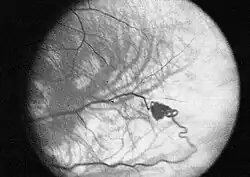

Narząd wzroku

Najwcześniej stwierdzaną w przebiegu choroby zmianą są naczyniaki zarodkowe siatkówki (haemangioblastoma retinae). Nieleczone guzy siatkówki prowadzą do stopniowej utraty wzroku.